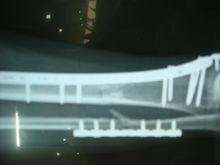

骨頭錯位● 及時檢查扭傷嚴重不妨對關節做x光照像檢查,因為嚴重扭傷與骨折經常不易區分。如確診,可在扭傷的肢體或手指部位鑄敷石膏模。

骨折的錯位可以因暴力的大小不同和作用方向的不同而發生多種移位,如發生成角、短縮、側方和鏇轉的移位,有的可以是單一種的移位,也可以是多種的移位。在下肢如發生短縮的移位,就可出現下肢的不等長;發生鏇轉的移位,在骨折癒合後,會發生走路時內或外八字的步態。